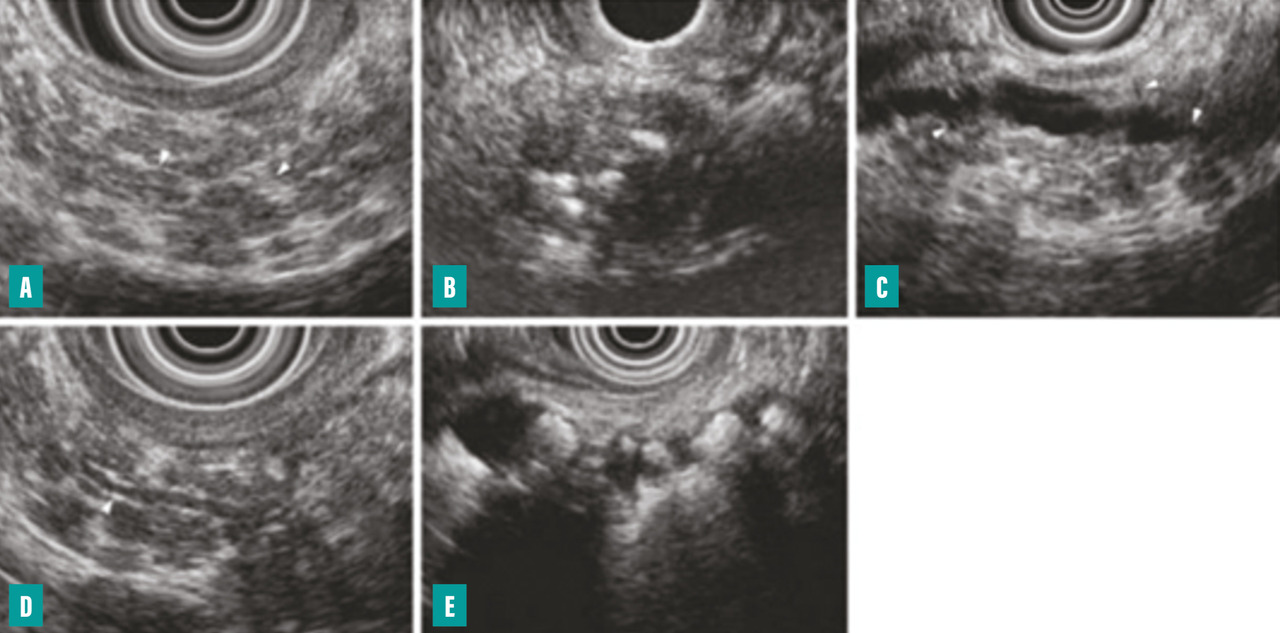

L’écho-endoscopie, apparue dans les années 1990, s’est positionnée comme l’examen de choix pour le diag­nostic des pancréatites chroniques débutantes pour lesquelles la TDM et l’IRM manquent de sensibilité. La classification de Rosemont a défini des critères majeurs et mineurs concernant le parenchyme pancréatique et les canaux (fig. 4).8 Mais cet examen se heurte à deux limites  : son manque de spécificité pour le diagnostic de pancréatite chronique et son caractère opérateur-dépendant.